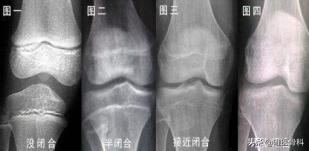

什么是骨骺线?骨骺线就是骨骺与干骺端之间的软骨,在X光片上表现为一条较宽的透光带,它随着年龄的增长而逐渐变短。